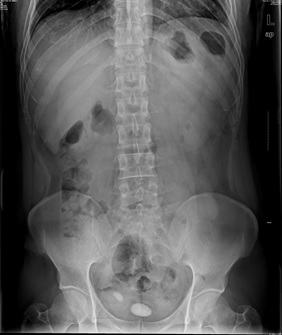

05卷-4.男,55歲,反復(fù)尿頻、尿痛、排尿困難半年(本題滿分2.00分)

本題答案:B

題目解析:【該題針對(duì)“X線-泌尿系結(jié)石”知識(shí)點(diǎn)進(jìn)行考核】